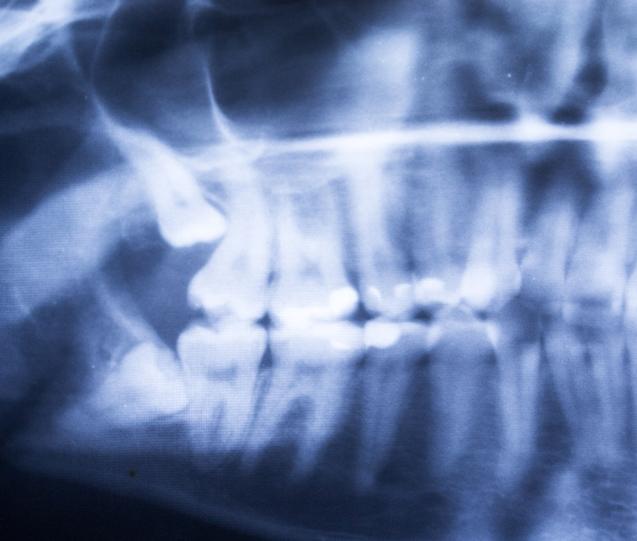

• Wisdom Tooth Removal: When wisdom teeth are impacted, misaligned, or causing crowding, removal may be recommended to prevent future complications. We offer wisdom tooth extractions with personalized care and support throughout the healing process.